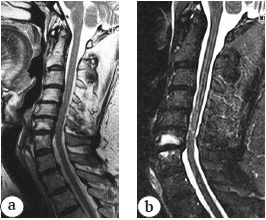

The patient was known to have a history of vertebrogenic cervical pain syndrome with irradiation to the left shoulder joint area since September 2020. He underwent staged courses of conservative analgetic (NSAIDs) and neurotropic therapy without any stable therapeutic effect. ENMG of the upper extremities (March 2021) showed the presence of preganglionic lesions of the C6-C8 spinal cord roots. MRI of the cervical spine in March 2021 revealed polysegmental degenerative-dystrophic changes in the C3-C7 spinal motion segments, stenosis of the spinal canal with the development of discoradicular conflict (Fig. 1).

Fig. 1. MRI (a — T2 images; b — STIR images): C3–С7 polysegmental degenerative changes, spinal canal stenosis, C6–С7 end plates oedema type I Modic, polysegmental myelopathy C4–С7